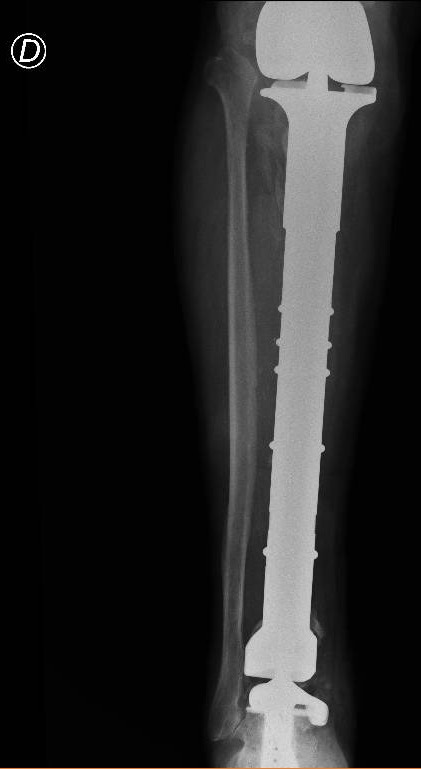

Il paziente veniva dunque trattato con una resezione del tumore con impianto di mega-protesi di tibia prossimale (cioè nell’area vicino al ginocchio). Ma i problemi non erano finiti. Dopo circa un anno dall’intervento, compariva una grave infezione della protesi impiantata e questo porta Mario a una serie di complessi interventi chirurgici, esitati con l’impianto di una protesi totale di gamba e di caviglia in titanio, rivestita in argento per proteggerlo dalle infezioni.

Basandosi sulla ricostruzione 3D della caviglia ‘bionica’ di Mario, i bioingegneri realizzano un “calco” della protesi custom-made con una stampante 3D, sul quale viene poi realizzata la protesi in titanio per l’impianto definitivo. Tutto è pronto per l’intervento al Gemelli che viene realizzato dal professor Carlo Perisano, professore aggregato dell’Università Cattolica del Sacro Cuore e dirigente medico presso la UOC di Ortopedia e Traumatologia di FPG, diretta dal professor Giulio Maccauro. Si tratta di un intervento unico nel suo genere, un esempio di come la medicina di precisione e personalizzata sia ormai entrata a far parte anche degli interventi chirurgici. Che dà i suoi frutti. A distanza di appena qualche giorno dall’intervento, Mario sta di nuovo in piedi sulla sua gamba ‘bionica’ arricchita di quest’ultimo gioiello tecnologico.

“Il paziente era stato sottoposto negli anni a diversi interventi chirurgici per il trattamento di un tumore osseo della tibia e delle successive complicanze che avevano compromesso anche le articolazioni del ginocchio e della caviglia – spiega il professor Perisano -. Nel 2019, è stato sottoposto a posizionamento di mega-protesi custom-made personalizzata di tibia totale ginocchio e caviglia, scongiurando così il rischio di una chirurgia demolitiva, ovvero dell’amputazione dell’arto, garantendo al paziente il ritorno alle normali attività quotidiane.

“Si tratta di interventi di estrema precisione – commenta il professor Giulio Maccauro, Ordinario di Ortopedia dell’Università Cattolica del Sacro Cuore -. Grazie ad un’accurata pianificazione pre-operatoria e allo strumentario dedicato ed estremamente sofisticato necessario per il confezionamento di queste protesi speciali (maschere di taglio, guide per posizionare le componenti protesiche e la protesi custom made stessa) ci è possibile effettuare interventi molto precisi, che riducono gli errori intraoperatori e guidano l’operatore nei processi decisionali e nell’atto chirurgico impensabili in passato”.